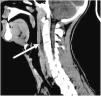

Se objetiva una colección laminar de 7,5×3,3×0,9cm, de paredes hipercaptantes, en espacio retrofaríngeo, extendiéndose desde C2 a C6 (fig. 1), y múltiples adenopatías laterocervicales bilaterales de aspecto reactivo (fig. 2). Con el hallazgo de posible absceso retrofaríngeo, se contacta con el servicio de otorrinolaringología, que decide ampliar el espectro de antibioterapia asociando meropenem y clindamicina, y manejo quirúrgico. Se realiza faringotomía posterior, con punción en diferentes puntos de la pared posterior, sin obtener material para cultivos.